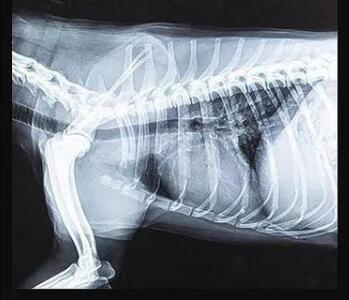

宠物dr专用平板拍摄效果

传统的平板探测器,相当于普通摄像机,对于拍摄急促呼吸状态下的宠物,成像效果存在着明显缺陷。而新一代宠物平板探测器,宛如高速摄像机,能够清晰记录动物每一个精准瞬间。